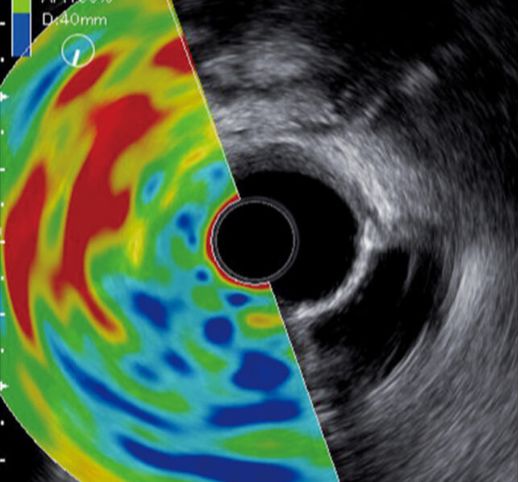

Aprovechando la potente claridad de imagen del Sistema de Imagen Endoscópica ELUXEO®, Fujifilm ofrece una experiencia de visualización directa excepcional en combinación con nuestras soluciones de imagen ultrasónica de alta calidad, líderes en la industria, lo que permite una gran versatilidad para el diagnóstico y tratamiento que ayuda a satisfacer las necesidades de su práctica.

El procesador de USE SU-1 Platinum es un equipo compacto, fácil de usar y totalmente compatible, que puede integrarse fácilmente en la torre del Sistema de Imagen Endoscópica ELUXEO® para una solución que ahorra espacio y ofrece una claridad de imagen confiable. El teclado plano del SU-1 también es fácil de limpiar y ofrece opciones tanto de panel táctil como de bola de seguimiento (trackball).